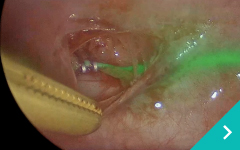

ミニマム創内視鏡下手術は腹腔鏡だけでは対処ができないような手術の際に、お腹にラッププロテクターという器具を設置して行う腹腔鏡と開腹手術を組み合わせた手術です。